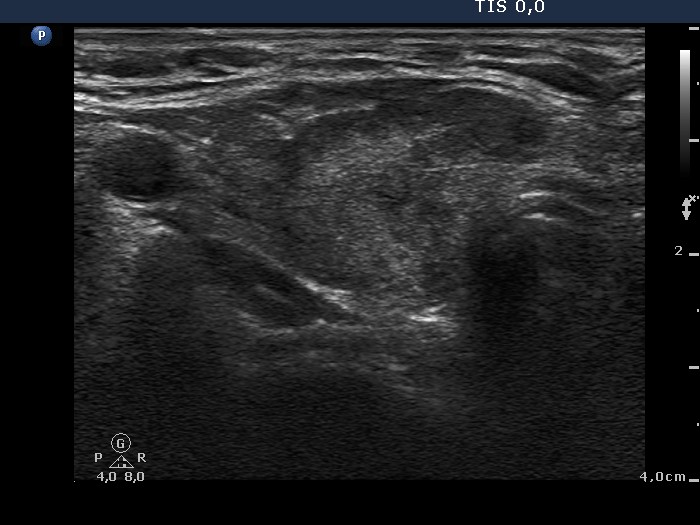

Third examination 18 months after initial examination (third row):

Clinical data: Another relapse of hyperthyroidism occurred 3 months ago. Thereafter, the dose of thyrostatic was increased.

Palpation: unchanged.

Result of blood test: subclinical hyperthyroidism (TSH 0.03 mIU/L, FT4 18.1 pM/L).

Ultrasonography: The pattern was the same.

Fourth examination 21 months after initial investigation (fourth and fifth rows):

Clinical presentation: The patient requested a second opinion. Multiple nodules including a suspicious one in the right lobe were described in another institute. Scintigraphy diagnosed multiple "cold" and warm" nodules in both lobes. Surgery was advised. The surgeon asked aspiration cytology of the hypoechogenic nodule described as suspicious on ultrasonography.

Results of blood tests: euthyroidism on daily 25 mg methimazole (TSH 3.78 mIU/L, FT4 10.9 pM/L).

Ultrasonography: unchanged.Cytology was performed from the hypoechogenic area in the upper part of the right thyroid.

Cytological diagnosis: benign pattern corresponding to previous dysfunction and isotope therapy.

The patient underwent total thyroidectomy. Histopathology disclosed diffuse goiter corresponding to Graves' disease and focal lymphocytic thyroiditis. There were no nodules.

Comment. It is worth analyzing the echo pattern of the thyroid. The small hypoechogenic area in the right lobe changed neither in size nor is shape nor in vascularization over 11 months.